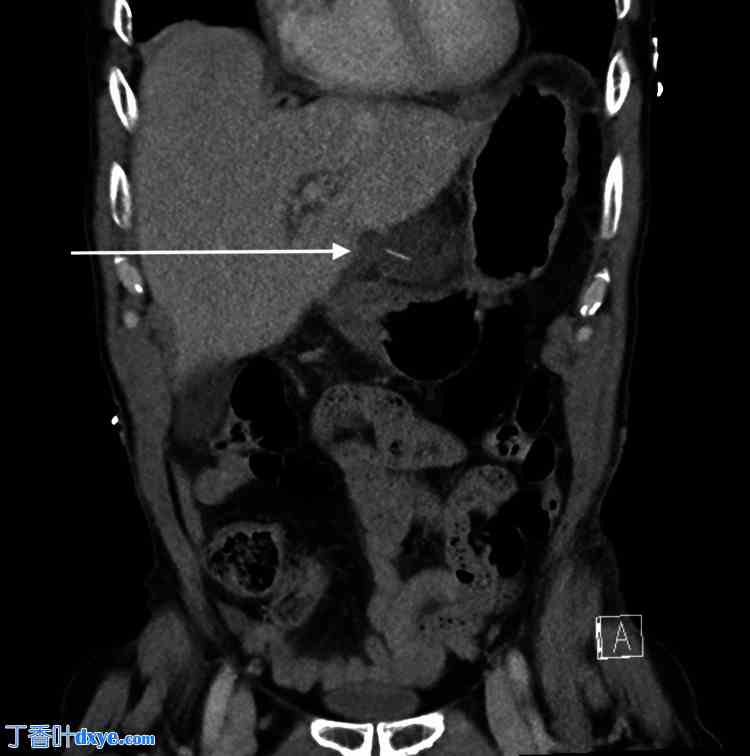

图2. 计算机断层扫描冠状位图像。

箭头指向小网膜囊内的低密度积液,中心的鱼骨距离胃小弯约25 mm。